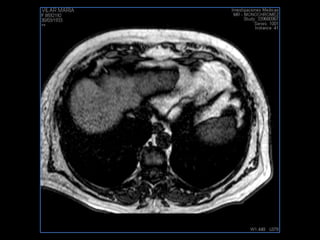

PROTOCOLO hígado graso AXIAL in phase y out phase AX T1 y AX fat sat +SAG T2  CON   GADOLINIO :  COR T1+AX T1(DIN) SAT: NO  FASE: RL THK: 4MM  COIL:  GAP: (FACTOR 1.4)  FOV: 40 CM NEX:2 SINCRONIZACION RESPIRATORIA EN 3 O 4 CICLOS ALE

PROTOCOLO hemocromatosis AXIAL supresión grasa /AX multieco en higado COR T2 AX T1 +SAG T2  CON   GADOLINIO :  COR T1+AX T1 SAT: NO  FASE: RL THK: 4MM  COIL:  GAP: (FACTOR 1.4) 1MM FOV: 40 CM NEX:2 SINCRONIZACION RESPIRATORIA EN 3 O 4 CICLOS ALE